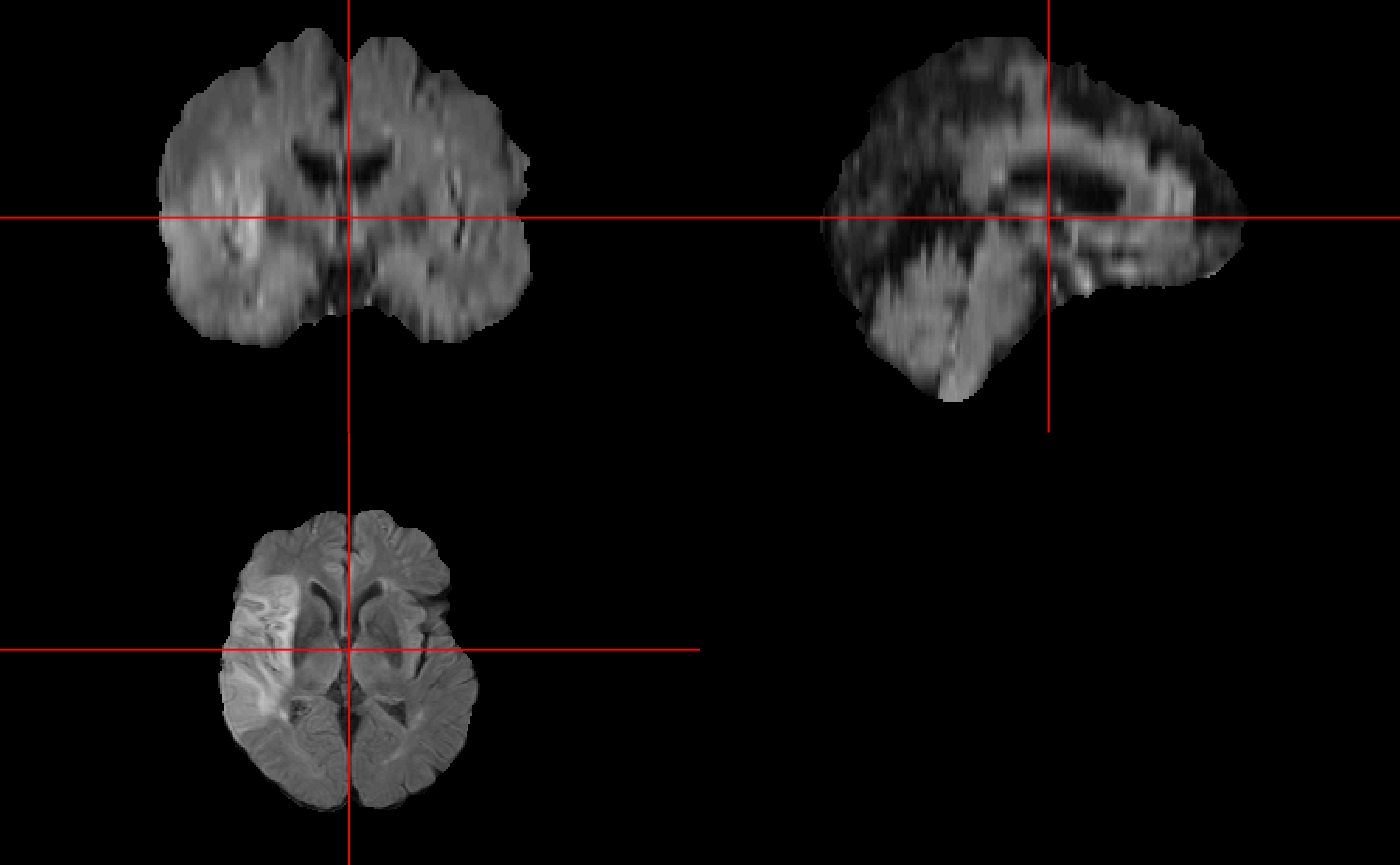

We can visualize the images thanks to John Muschelli’s ortho2() function in his neurobase package.

Now we can visualize the score images